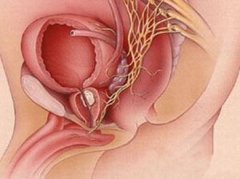

子宫颈的血供主要来自子宫动脉,其在宫旁组织到达子宫外侧,距宫颈内口水平约2 cm横跨输尿管至子宫侧缘,此后分为上、下两支,下支分布于子宫颈及阴道上段,称宫颈阴道支,静脉相伴而行。

子宫颈的神经主要来自骶前神经丛,大部分在宫颈旁形成骨盆神经丛,分布于宫体、宫颈等。